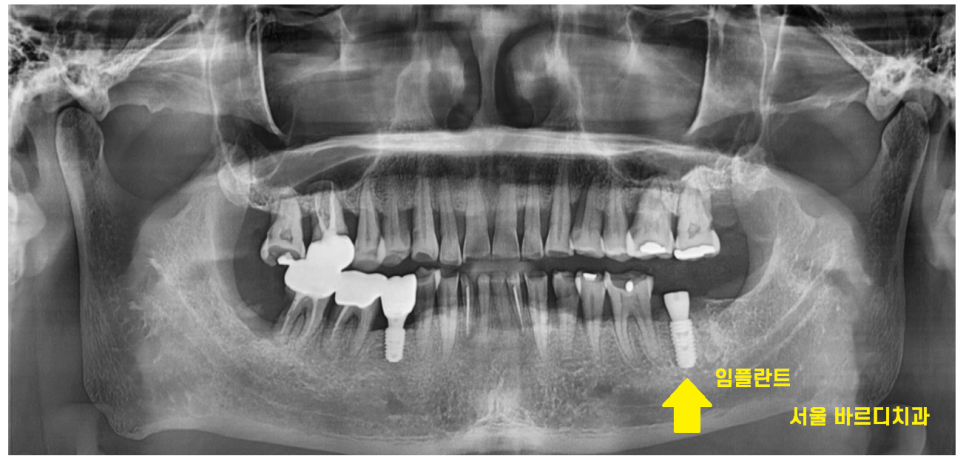

23.10.16

결국 이가 반으로 갈라져서

환자분은 발치 후 임플란트 치료를 진행하셨답니다.

오늘은 망월동 치과를 방문해주신

안타까운 환자분의 이야기를 들려드렸습니다.

신경치료가 끝나고

치아를 덮어서 보호해주었더라면

최소 몇년은 더 자기 치아를 쓰실 수 있으셨을텐데 ..